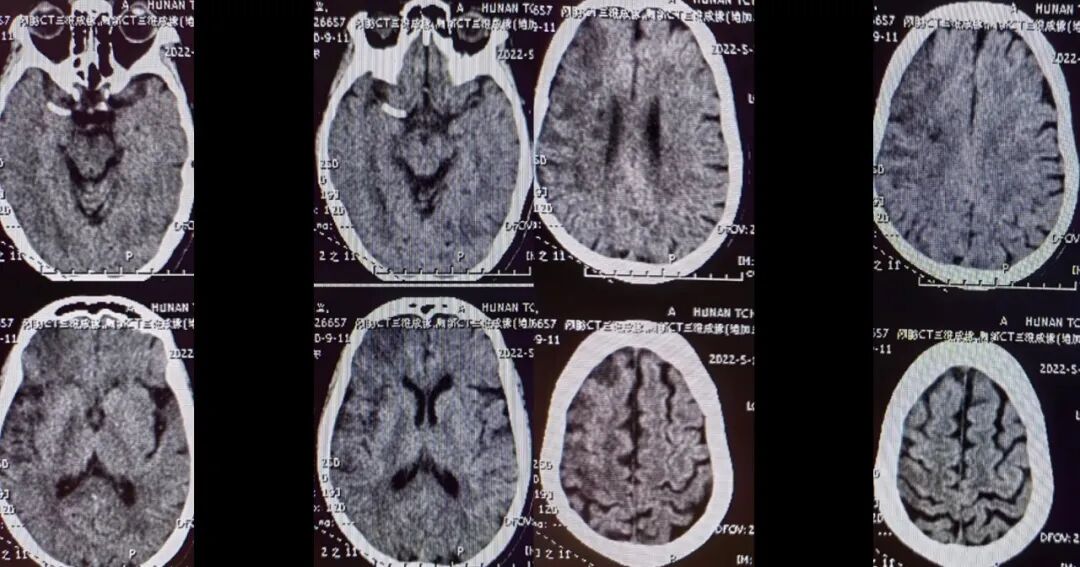

术后影像及随访

(术后8h CT)右侧放射冠区、右侧基底节区、右侧额叶多发急性梗死。

导丝怎么扩【载药时代 球扩天下】NOVA DES®颅内药物洗脱支架在大脑中动脉重度狭窄的应用二例!_https://www.jmylbn.com_新闻资讯_第17张

(术后7d CT)右侧放射冠区、右侧基底节区、右侧颞叶、额叶多发急性梗死。

导丝怎么扩【载药时代 球扩天下】NOVA DES®颅内药物洗脱支架在大脑中动脉重度狭窄的应用二例!_https://www.jmylbn.com_新闻资讯_第18张

(术后14d CTA)RMCA-M1支架植入术后改变。

导丝怎么扩【载药时代 球扩天下】NOVA DES®颅内药物洗脱支架在大脑中动脉重度狭窄的应用二例!_https://www.jmylbn.com_新闻资讯_第19张

导丝怎么扩【载药时代 球扩天下】NOVA DES®颅内药物洗脱支架在大脑中动脉重度狭窄的应用二例!_https://www.jmylbn.com_新闻资讯_第20张

NOVA DES®应用——2022年随访:

2022年6月23日:左上肢肌力2+级;左下肢肌力5-级;可流利行走;言语欠流利;神志清楚;NIHSS 5分;mRS 2分。